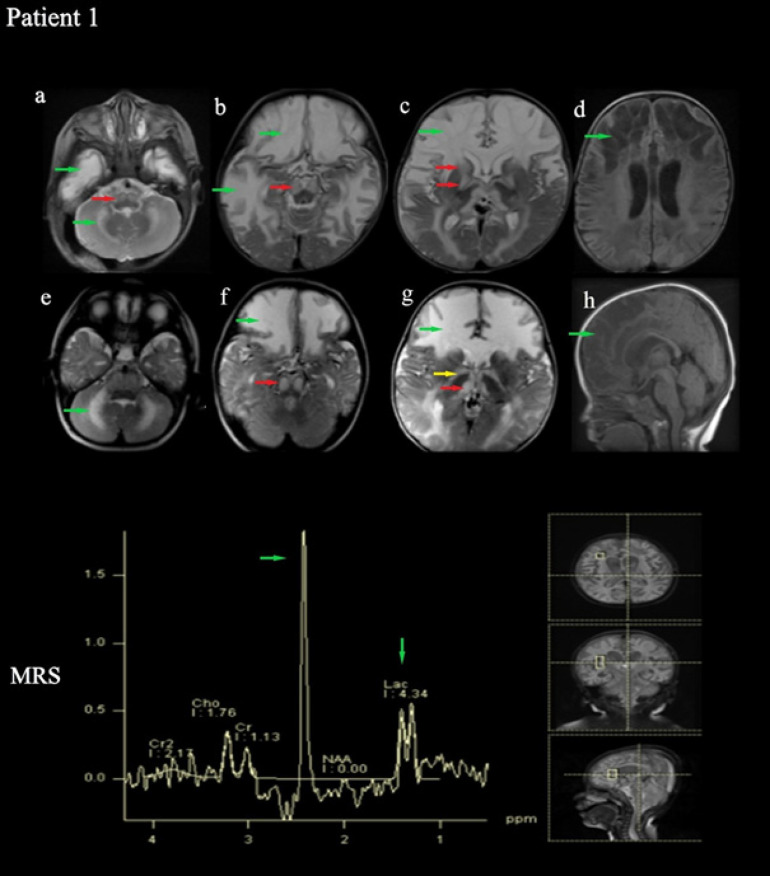

The Succinate Dehydrogenase (SDH) enzyme is known as Complex-II in the electron transport chain. This study reports the clinical and molecular investigations of three pediatric patients (two of whom are siblings), with histochemical and biochemical evidence of a severe, isolated complex II deficiency due to SDH gene mutations. The patients presented with severe hypotonia, developmental delay, spasticity, macrocephaly, and megalencephaly. Magnetic Resonance Imaging (MRI) revealed signal changes in the frontal, temporal, parietal, occipital cerebral, and cerebellar white matter, corpus striatum, thalamus, substantia nigra, inferior olivary nucleus, pyramidal tracts at the level of the pons and posterior limb of the internal capsule. Other typical findings involved a high succinate peak at 2.42 ppm and lactate peak at 1.3 ppm in Magnetic Resonance Spectroscopy (MRS). The siblings presented due to compound heterozygous c.143A>T (p. Asp48Val) and c.308T>C (p. Met103Thr) SDHB mutations, while the other patient presented due to compound heterozygous c.1754G>A (p. Arg585Gln) and c.1786G>C (p. Asp596His) SDHA mutation. The demonstration of succinate peak, particularly MRS, is highly diagnostic regarding SDH deficiency. MRS should be a standard part of routine radiological exams when there is a suspicion of a neurometabolic disease, especially mitochondrial disorders. Additionally, employing Next-Generation Sequencing (NGS) is advisable for patients as it allows for accurate diagnosis without requiring invasive procedures like muscle biopsies.